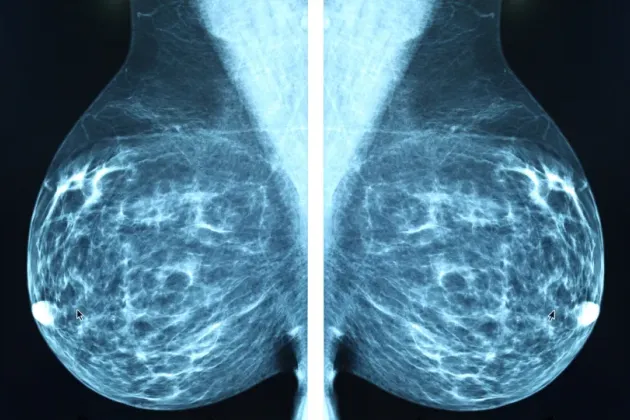

AI model from Lund University indicates four out of ten breast cancer patients could avoid axillary surgery

A project at Lund University in Sweden has trained an AI model to identify breast cancer patients who could be spared from axillary surgery. The model analyses previously unutilise...